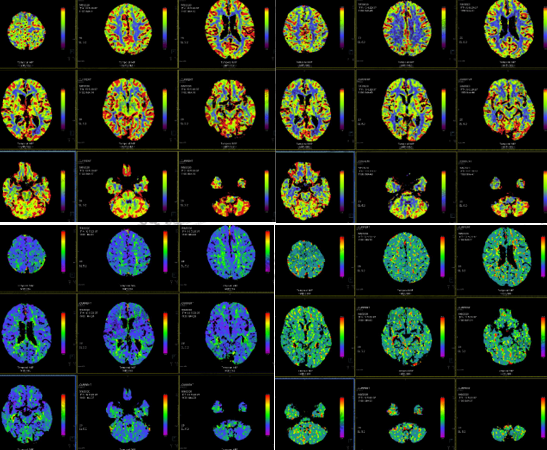

病史:男,79岁,怀疑早期脑缺血病变行颅脑灌注成像,如图所示:

颅脑灌注成像示脑实质内未见明显异常灌注区,于双侧大脑半球对称位置分别选取ROL,分别为ROL、ROL-m。ROL的CBF、CBV、MTT、TTD值分别为65.23、3.82、3.85、3.51,ROL-m的CBF、CBV、MTT、TTD值分别为63.77、3.75、3.94、3.72。双侧ROL区域相应参数数值均未见明显差异。动态增强的时间-信号强度曲线中,ROL与ROL-m及相同层面的平均值未见明显差异。

注:CBF-脑血流量;CBV-脑血容量;MTT-平均通过时间;TTD-延迟时间;TTP-达峰时间

结果:脑灌注成像未见明显异常。